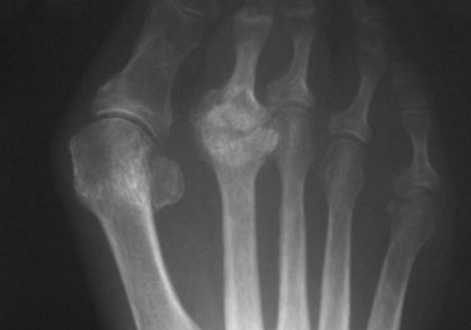

- Болезнь КеллераII. На снимках выявляются патологические изменения в головке пораженной плюсневой кости. В зависимости от срока заболевания может обнаруживаться остеопороз, уплотнение и деформация головки плюсневой кости, ее патологический перелом и дефрагментация.

КТ стопы. Болезнь Келера-2 (остеохондропатия головки 3-й плюсневой кости: снижение высоты головки вследствие остеонекроза, с наличием свободного костно-хрящевого фрагмента).

Болезнь Келлера, или болезнь Фрайберга, - аваскулярный некроз и перелом головок 2,3,4 плюсневых костей. Данное заболевание, распространённое главным образом среди женщин в возрасте 13-18 лет, чаще всего поражает головку 2-й плюсневой кости, особенно её тыльную поверхность. Часто встречается у лиц с длинной 2-й плюсневой костью (стопа Мортона). Патофизиология заболевания связана с постоянной микротравматизацией из-за перегрузки и последующим остеонекрозом из-за нарушения кровоснабжения.

Определяется деформация и уплощение головки 2, 3, 4 плюсневой кости. На фоне разряжения структуры костной ткани головки дифференцируются плотные островки с четкими, неровными контурами. Дистальный метафиз 2 плюсневой кости несколько утолщен, по всей видимости, за счет периостальных наслоений. Суставная щель во 2 плюсне - фаланговом суставе расширена.

Суставные поверхности, образующие плюсне-фаланговый сустав, инконгруэнтны, форма суставных поверхностей деформирована, уплощена, склерозирована в области . Величина суставных поверхностей увеличена за счет краевых костных разрастаний. Контуры замыкательных пластинок эпифизов ровные, чёткие. Подхрящевой (субхондральный) остеосклероз, как свидетельство функциональной несостоятельности суставных хрящей и свидетельствующий о перегрузке костной ткани, определяется в области . По краям суставных поверхностей определяются костные разрастания (свидетельствуют о функциональной несостоятельности суставных хрящей).

ДИАГНОСТИЧЕСКОЕ ЗАКЛЮЧЕНИЕ:

Остеохондропатия головки 2 плюсневой кости - болезнь Келера 2 правой стопы, картина деформирующего артроза 2 плюсне-фалангового сустава 2 (второй) стадии по классификации Н.С. Косинской.